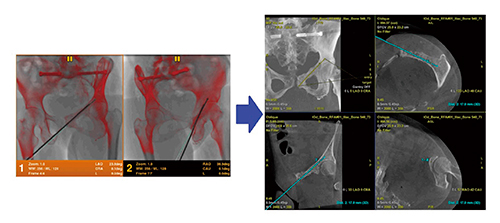

“Trajectory Planning”というアプリケーションを用いると,術前CBCTのオブリーク画像上からエントリーポイントとターゲットポイントを指定することで,これらの間を結ぶ穿刺軌道が自動で算出される。そして,ターゲット位置や穿刺軌道を透視上に表示しエントリーポイントとターゲットが一直線上で重なるbull’s eye viewが自動表示され,術前に穿刺プランの確認を行うことができる。術中は穿刺プランを3Dロードマップ上に表示することができ,かつ,bull’s eye viewのtangent方向であるprogress viewをワンタッチで切り替えることも可能であり,穿刺手技をサポートすることができる。

加えて,手技中に穿刺針などの対象物が視野内にある状態で,2方向から透視画像を収集すると,これらの画像から対象物を3Dで再構成し,これを冒頭に撮影したCBCT画像上に重ねて表示可能となる(図6)。これにより,手技中2方向からの透視のみでCBCTのオブリーク画像上に現在の穿刺針の位置を表示できるため,例えば,穿刺針の深度や方向を3D画像上で自由に角度を変えながら詳細確認が可能となる。進行する手技の中で必要に応じて正確性を確認しながら,手技精度を高めるためのサポートが可能になると考えられる。